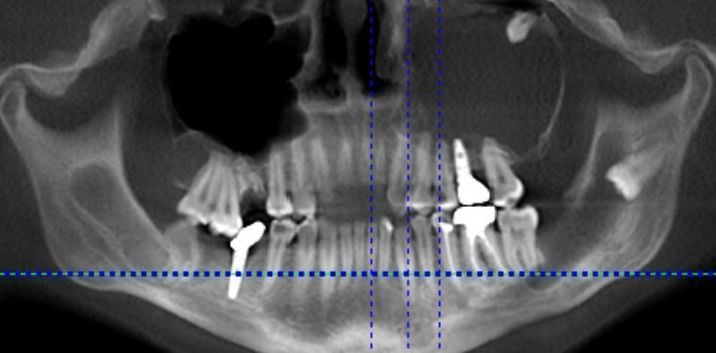

Digitale Volumentomographie

Die digitale Volumentomographie ist ein präzises röntgenologisches 3-D Verfahren zur Darstellung knöcherner Strukturen des gesamten Kopfbereiches. Je nach Fragestellung können auch kleinere Ausschnittsdarstellungen vorgenommen werden. Die Technik gleicht einer konventionellen Übersichtsaufnahme, wobei hier jedoch der Mund geschlossen bleiben kann. Die generierten Aufnahmen gleichen denen eines konventionellen CT, jedoch bedingt die Aufnahmetechnik für zahnärztliche Fragestellungen eine Reihe Vorteile:

- Wahlweise höhere Auflösung

- Geringere Strahlenbelastung

- Weniger Metallartefakte ( Aufnahmequalität mindernde Störungen) durch Zahnfüllungen und prothetische Rekonstruktionen

Ihr Zahnarzt oder Arzt überweist Sie häufig mit einer speziellen Fragestellung wie

- Klärung des Knochenangebots vor einer Implantatversorgung

- Verlauf des Unterkiefernerven vor Weisheitszahnentfernungen

- Lage und Prognose retinierter Zähne (Kieferorthopädie)

- Frakturausschluss

- Zystenausdehnung

- unklare Schwellungen-, Schmerzen

- anatomische Situation der Nasennebenhöhlen (ORL)

Zuweiser: Patienten können direkt über die Homepage zur digitalen Volumentomographie angemeldet werden.